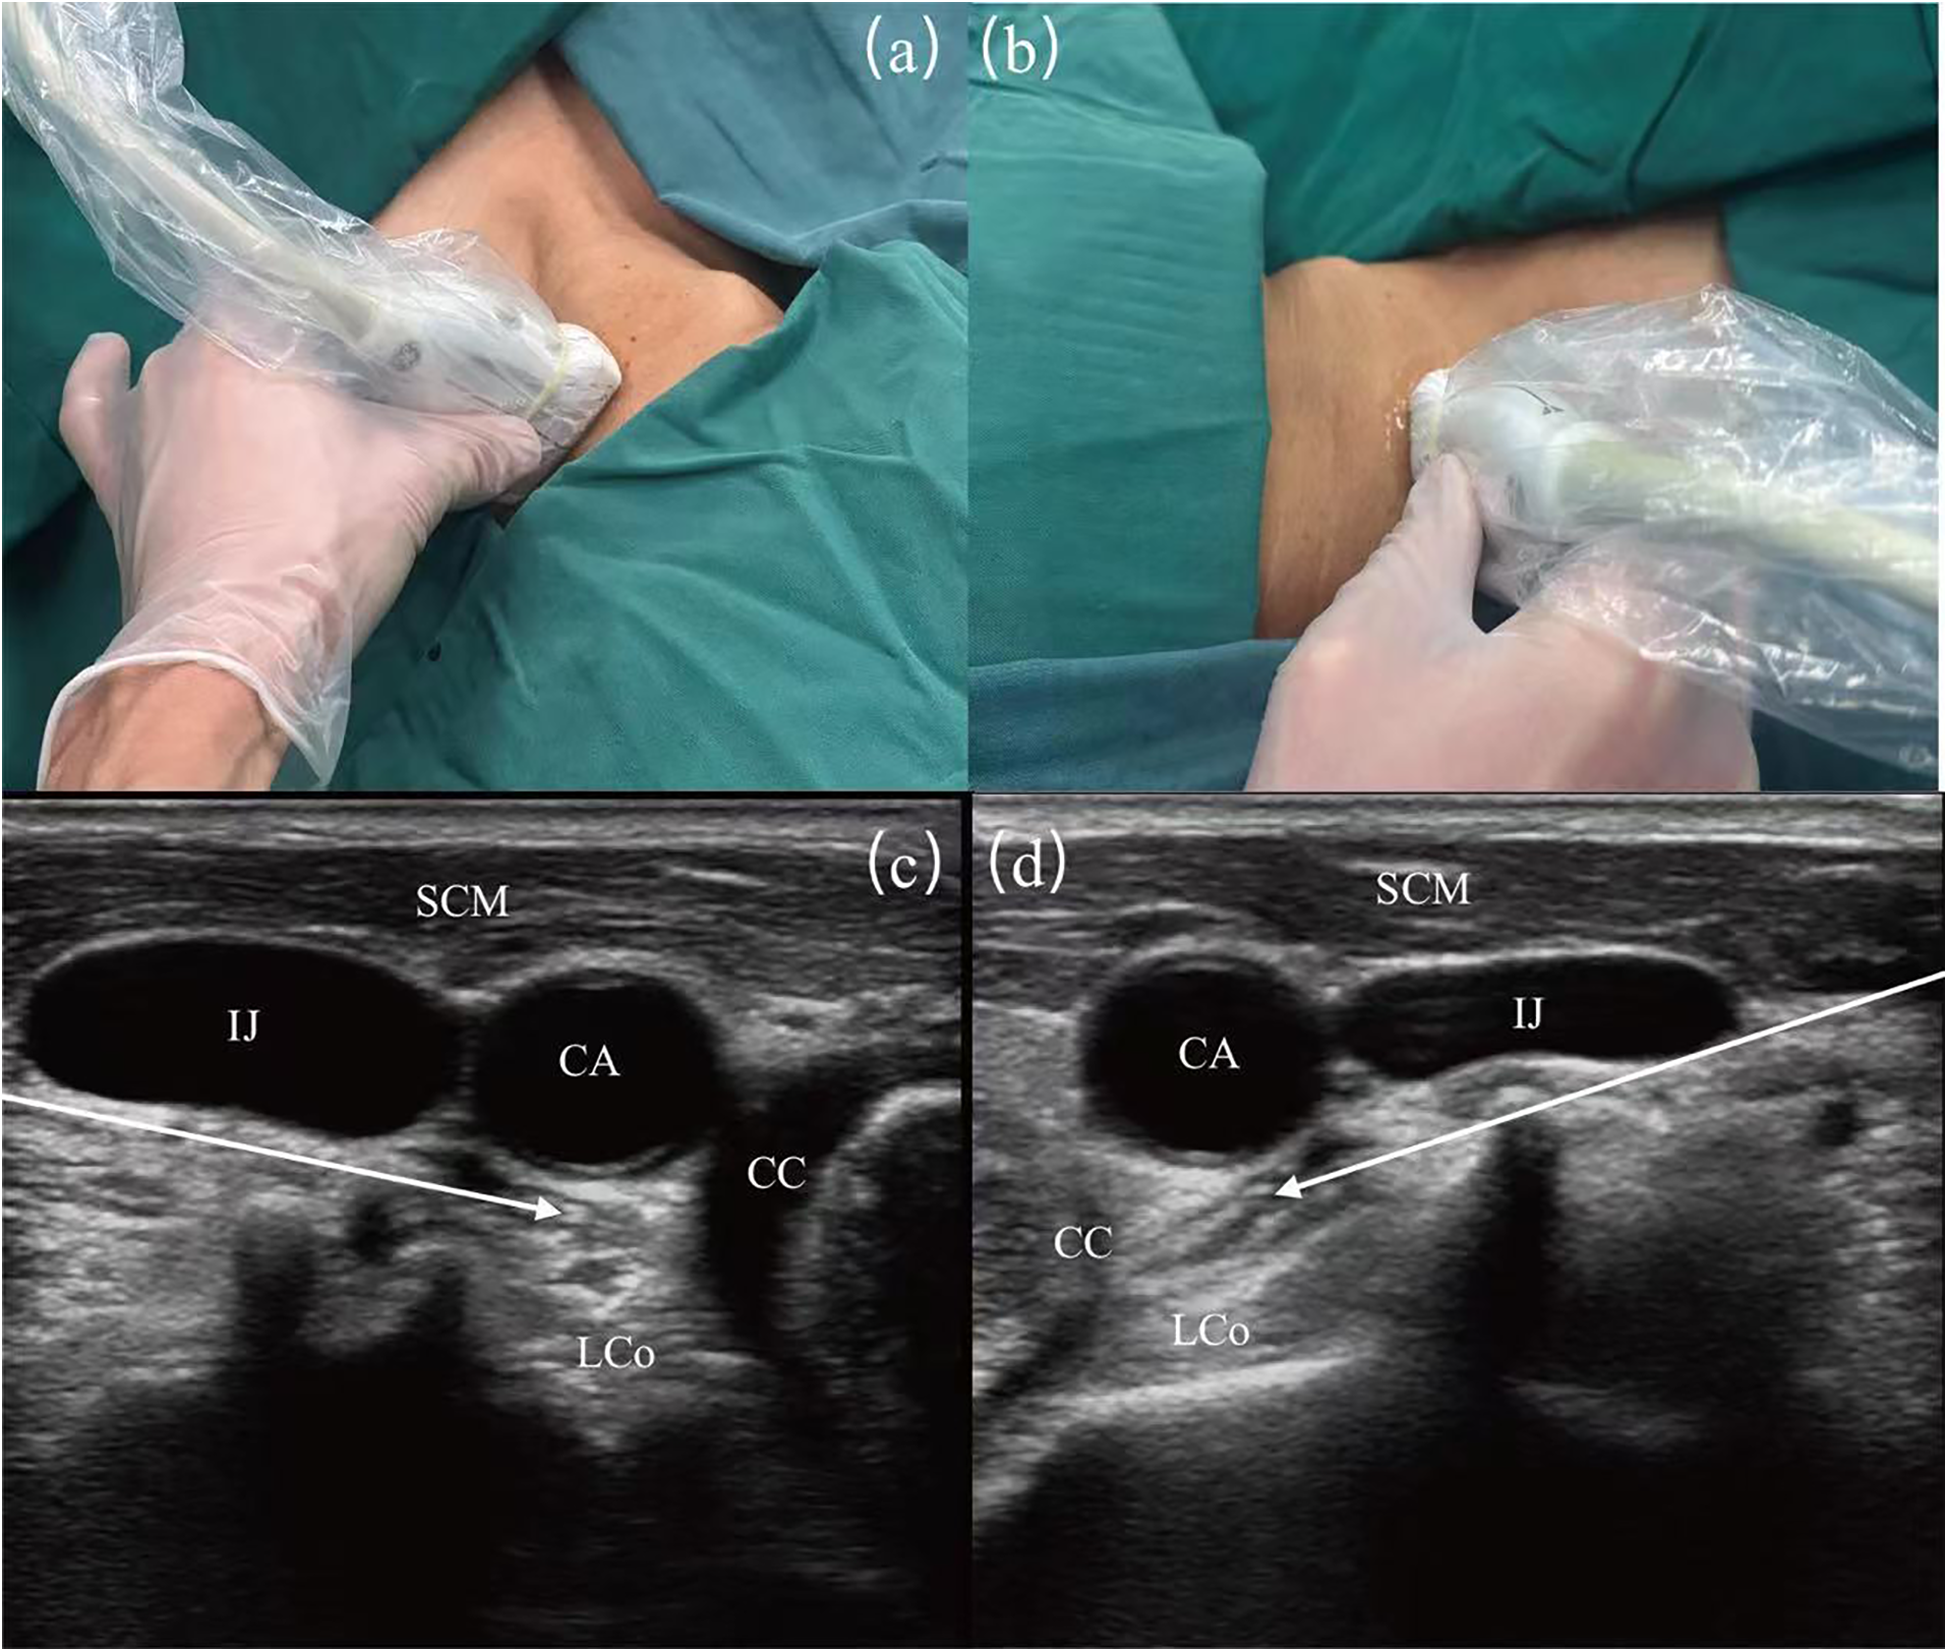

Techniques described for SGB involve anterior paratracheal, lateral, anterolateral, superior, and posterior approaches. Although SGB have been used in clinical practice for more than 70 years, the literature indicates a variable success rate (16%–100%) (23, 24). With ultrasound guidance, SGB procedures have become more accurate and standardized to ensure the accuracy of injection sites (25). Utilizing ultrasound guidance allows for the accurate identification of the appropriate fascial plane, and positioning the needle at the C6 level facilitates the caudal dispersion of the injectate to the stellate ganglion located at the C7-T1 level. This technique enhances the efficacy and precision of sympathetic nerve blocks while utilizing a reduced volume of injectate. Furthermore, ultrasound-guided stellate ganglion blocks improve procedural safety by allowing direct visualization of vascular structures (e.g., inferior thyroid artery, carotid arteries, vertebral artery, carotid sheath) and soft tissue structures (e.g., thyroid gland, esophagus, nerve roots) (Figure 1) (26).

Figure 1

Image guidance for stellate ganglion block (SGB) under ultrasound. (a) Surface ultrasound position diagram of left SGB. (b) Surface ultrasound position diagram of right SGB. (c) Guided diagram for left SGB under ultrasound guidance. (d) Guided diagram for right SGB under ultrasound guidance. SCM, sternocleidomastoid muscle; CA, carotid artery; IJ, internal jugular vein; LCo, longus colli muscle; CC, circular cartilage. The white arrows show the path of the puncture needle, with the arrowheads indicating the location of the stellate ganglion.